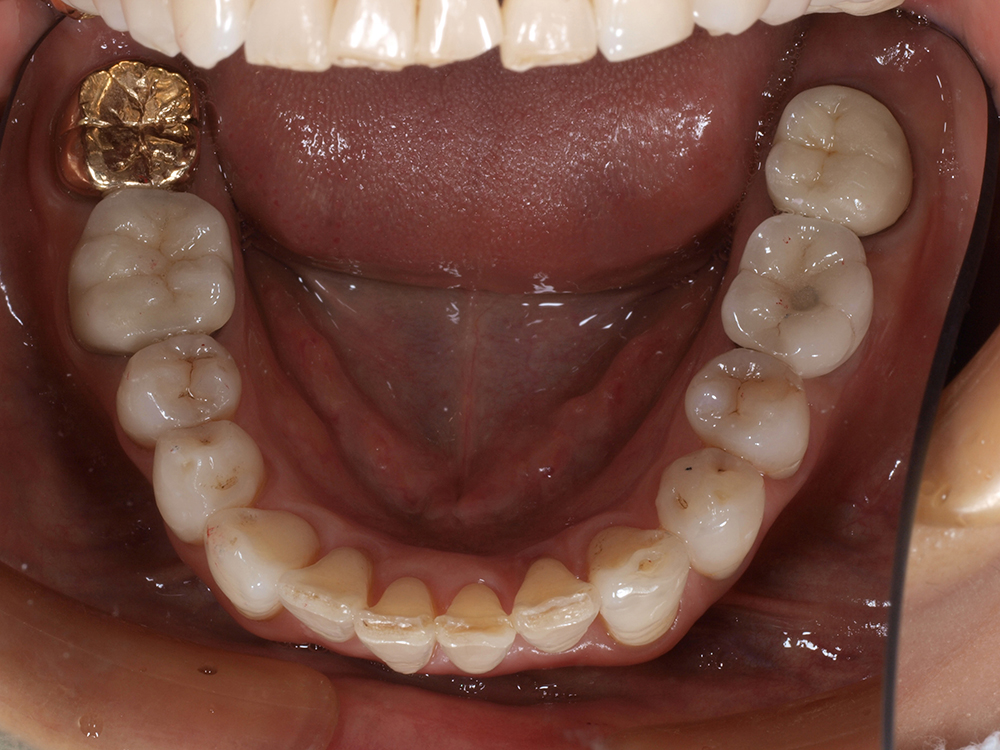

55歳 男性

- 主訴

- 前歯でしか咬めなく、食事を採るのに非常に困難で辛い

- 処置内容

- 上顎6本、下顎3本

- 治療費用

- 上顎:約230万(税込)下顎:約120万(税込)

- 治療期間

- 上顎:1年(仮歯まで8か月)下顎:8か月(仮歯まで5か月)

- リスク

- 上部構造物、仮歯の破折、術後の腫れ(3日)、人工歯根脱落リスクがあります